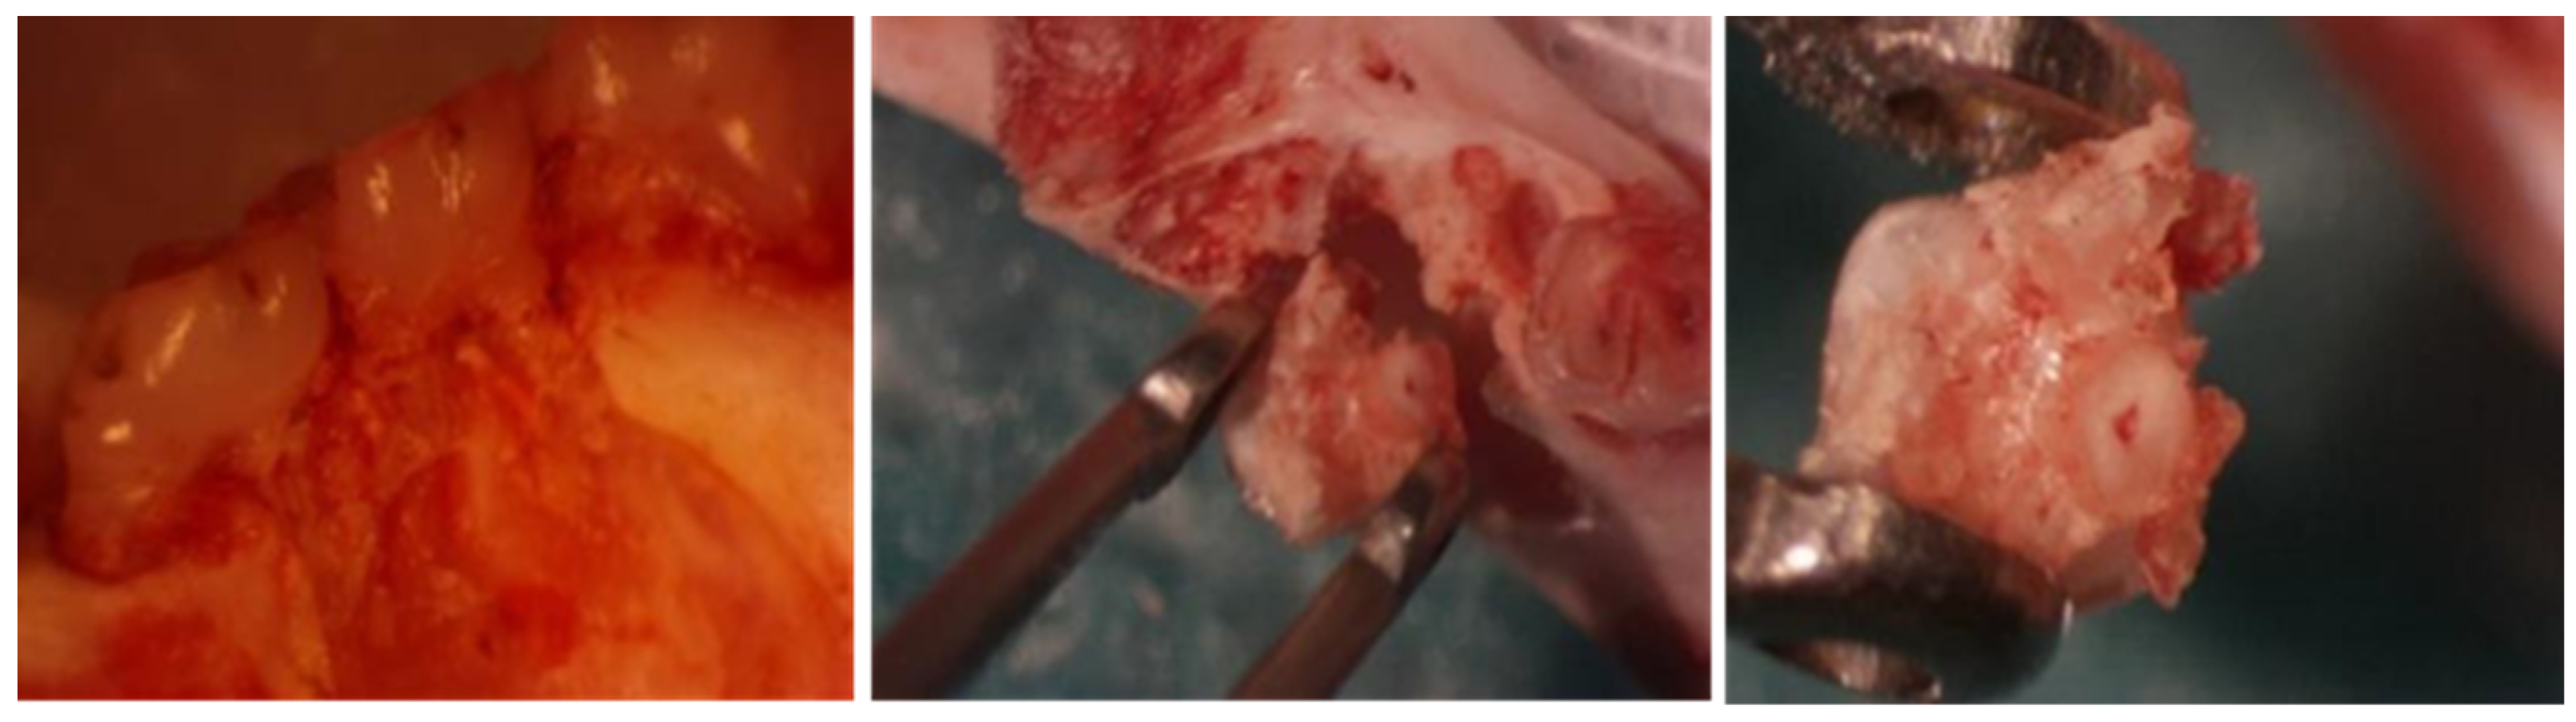

2.6. Macroscopic Study

3.3. Descriptive Histological Analysis